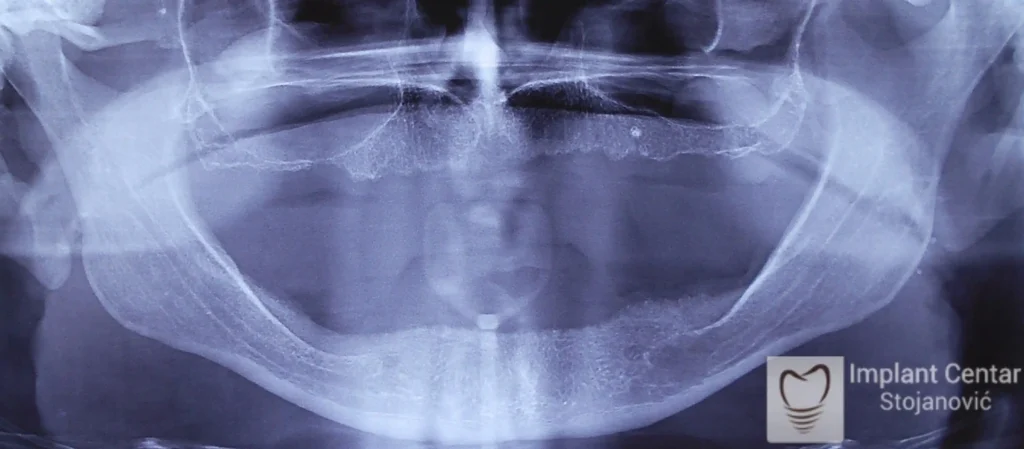

Na slici 1. i slici 2. prikazan je izgled pacijenta pre početka terapije – klinički i rendgenološki.